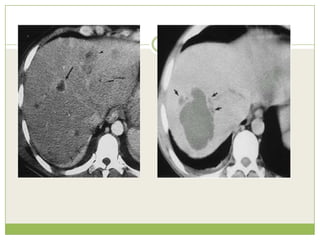

• La TAC puede dar mayor resolución de la

imagen y ser más sensible pero no

proporciona datos más específicos.TAC

Se muestra lesion quistica de gran

tamaño con signos de ruptura

intrahepatica, localizada en los

segmentos VI y VII del higado

secundario a absceso amibiano